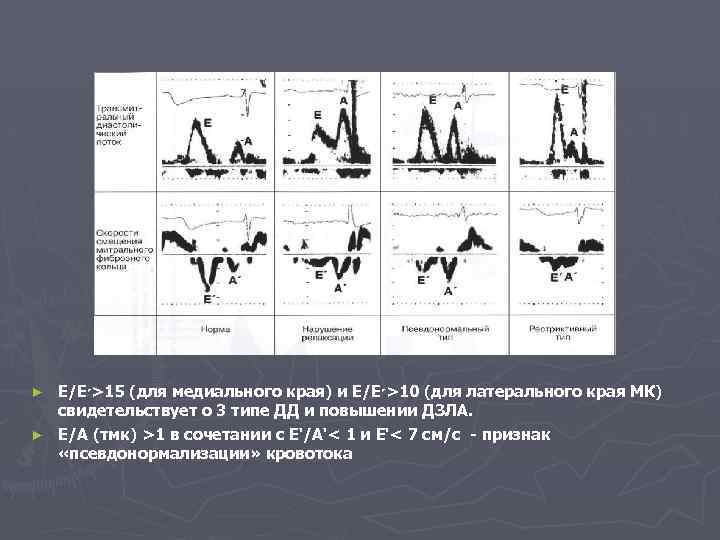

Е/Е ( 51>׳ для медиального края) и Е/Е ( 01>׳ для латерального края МК) свидетельствует о 3 типе ДД и повышении ДЗЛА. ► Е/А (тмк) >1 в сочетании с E‘/А‘< 1 и E‘< 7 см/с - признак «псевдонормализации» кровотока ►